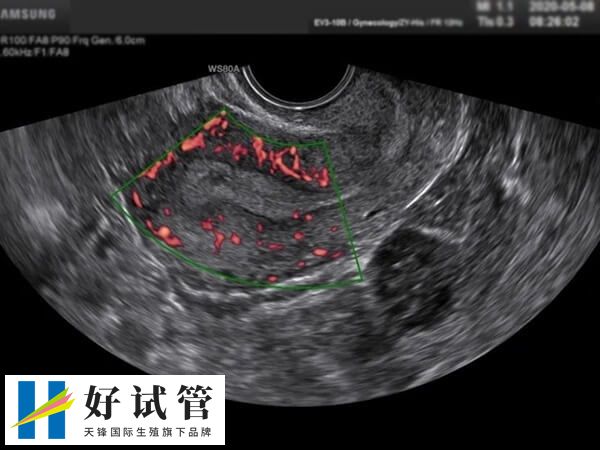

做试管婴儿移植成功率之后,患者进行的第二次超声检查一般在移植后45-50天进行,具体时间取决于一超的检查结果。二超的目的是进一步了解胚胎的发育情况,包括胎心和胎芽的存在与否。

在进行试管婴儿治疗的过程中,如果第一次超声检查(即一超)没有发现孕囊,建议延迟一周左右再次进行彩超的复查,以确认是否妊娠。如果发现胎心、胎芽的发育,说明胚胎生长发育良好。此外,二超检查如果推迟,通常不建议超过一个月。如果需要推迟,最好与个人的医生沟通并根据具体情况进行调整。